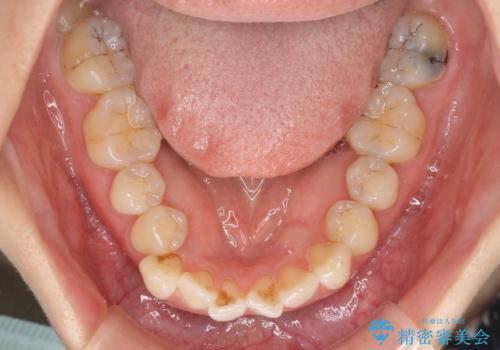

- 重なった前歯を邪魔に感じ、汚れも溜まりやすいことを気にして来院された患者様です。

右上前から2番目の歯が内側に転位しているため、上顎の正中は右にずれていました。

右上4番目の歯を抜歯し、上顎裏側に補助装置を装着して左の歯列全体を後方に移動させながら、正中を合わせるようにして行くこととしました。

内側に転位していた歯はきれいに歯列に収まり、清掃性が著しく改善しました。

元々神経の失活してしまっている前歯2本は変色が目立つようになってきたため、今後セラミッククラウンによる補綴治療を行う予定です。